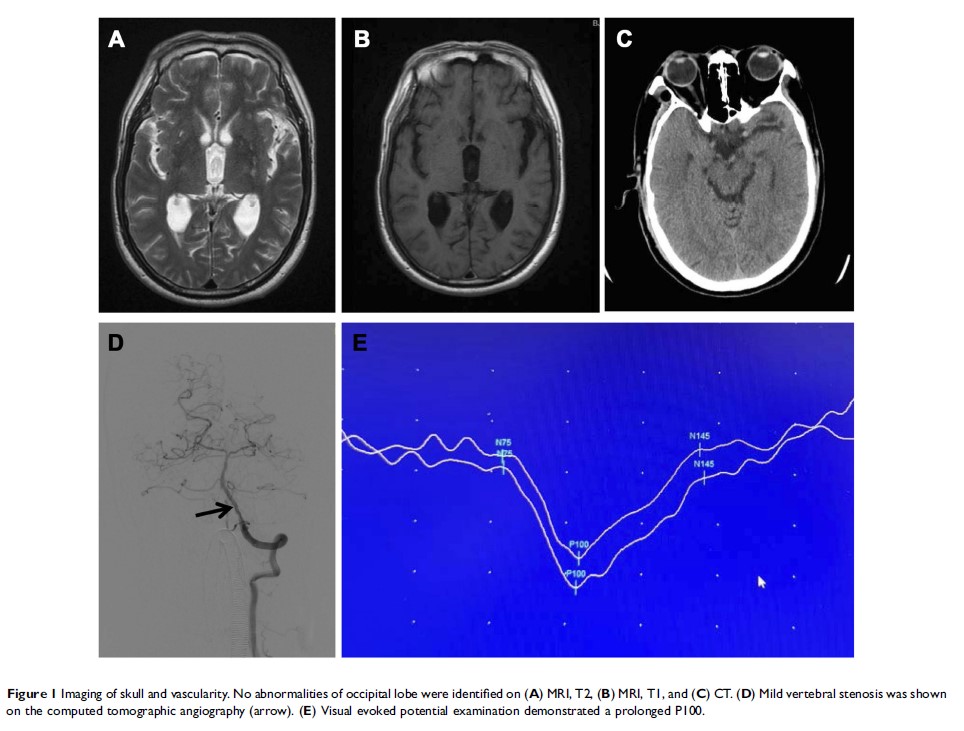

施行脑血管造影后皮层性视损伤的潜在危险因素:回顾性研究